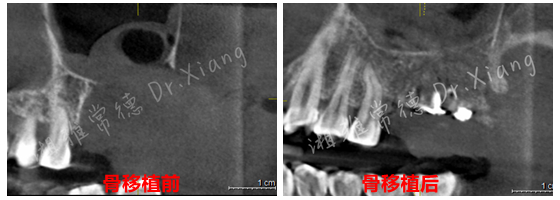

2024年末,該患者因外院不正規(guī)的拔牙造成左上頜大面積骨缺損。為尋求頜骨修復(fù),在常德多家醫(yī)療機構(gòu)就診,均告知難度大建議前往長沙?;颊卟幌氡疾?,經(jīng)朋友介紹后來到湘雅常德醫(yī)院就診??谇豢浦魅挝闂澖釉\了患者并為患者制定了詳細的治療計劃。伍棟主任指出:患者因拔牙造成頜骨大面積缺損,目前需要分二步處理。第一,先行頜骨缺損的骨移植;第二,待骨移植成功后,再行缺牙的種植修復(fù)。經(jīng)過周密的術(shù)前規(guī)劃和準備,口腔頜面外科團隊在全身麻醉下為患者成功施行了“游離髂骨移植修復(fù)術(shù)+牙槽植骨成形術(shù)”。手術(shù)團隊巧妙地以患者自身的髂骨作為移植材料,采用數(shù)字化3D設(shè)計與打印技術(shù),在術(shù)中精準截取髂骨并完成上頜骨缺損的定制化重建,成功恢復(fù)頜骨及牙槽嵴的生理性高度與寬度,實現(xiàn)解剖結(jié)構(gòu)的精準復(fù)原,并應(yīng)用了微型鈦板鈦釘內(nèi)固定系統(tǒng)來確保移植骨的穩(wěn)定愈合。

經(jīng)過9個月骨愈合后,患者復(fù)查錐形束CT,骨愈合十分滿意。9月中旬,向峰醫(yī)師種植團隊成功為患者實施了第二步的手術(shù),取出內(nèi)固定裝置的同時為患者成功微創(chuàng)的植入2枚種植體,完成了患者左上頜區(qū)域的軟硬組織的自然恢復(fù)和改建。